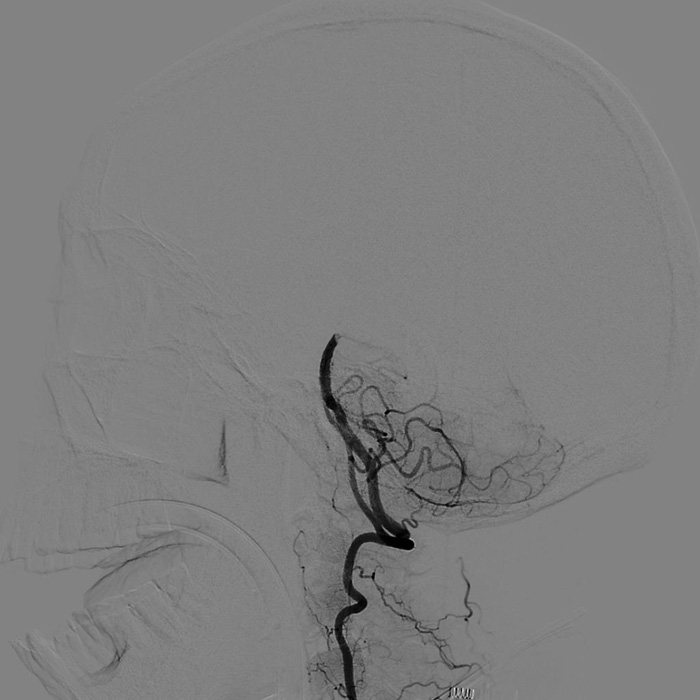

??? 22:10? 王大伯病情進一步加重,神經(jīng)外科戴偉民主任醫(yī)師團隊、麻醉師和介入室的醫(yī)護人員全部已經(jīng)到位。全腦血管造影顯示栓塞部位在基底動脈末端,雙側(cè)小腦上動脈及雙側(cè)大腦后動脈開口處完全閉塞。

手術(shù)前血管造影提示雙側(cè)小腦上動脈及雙側(cè)大腦后動脈開口處完全閉塞